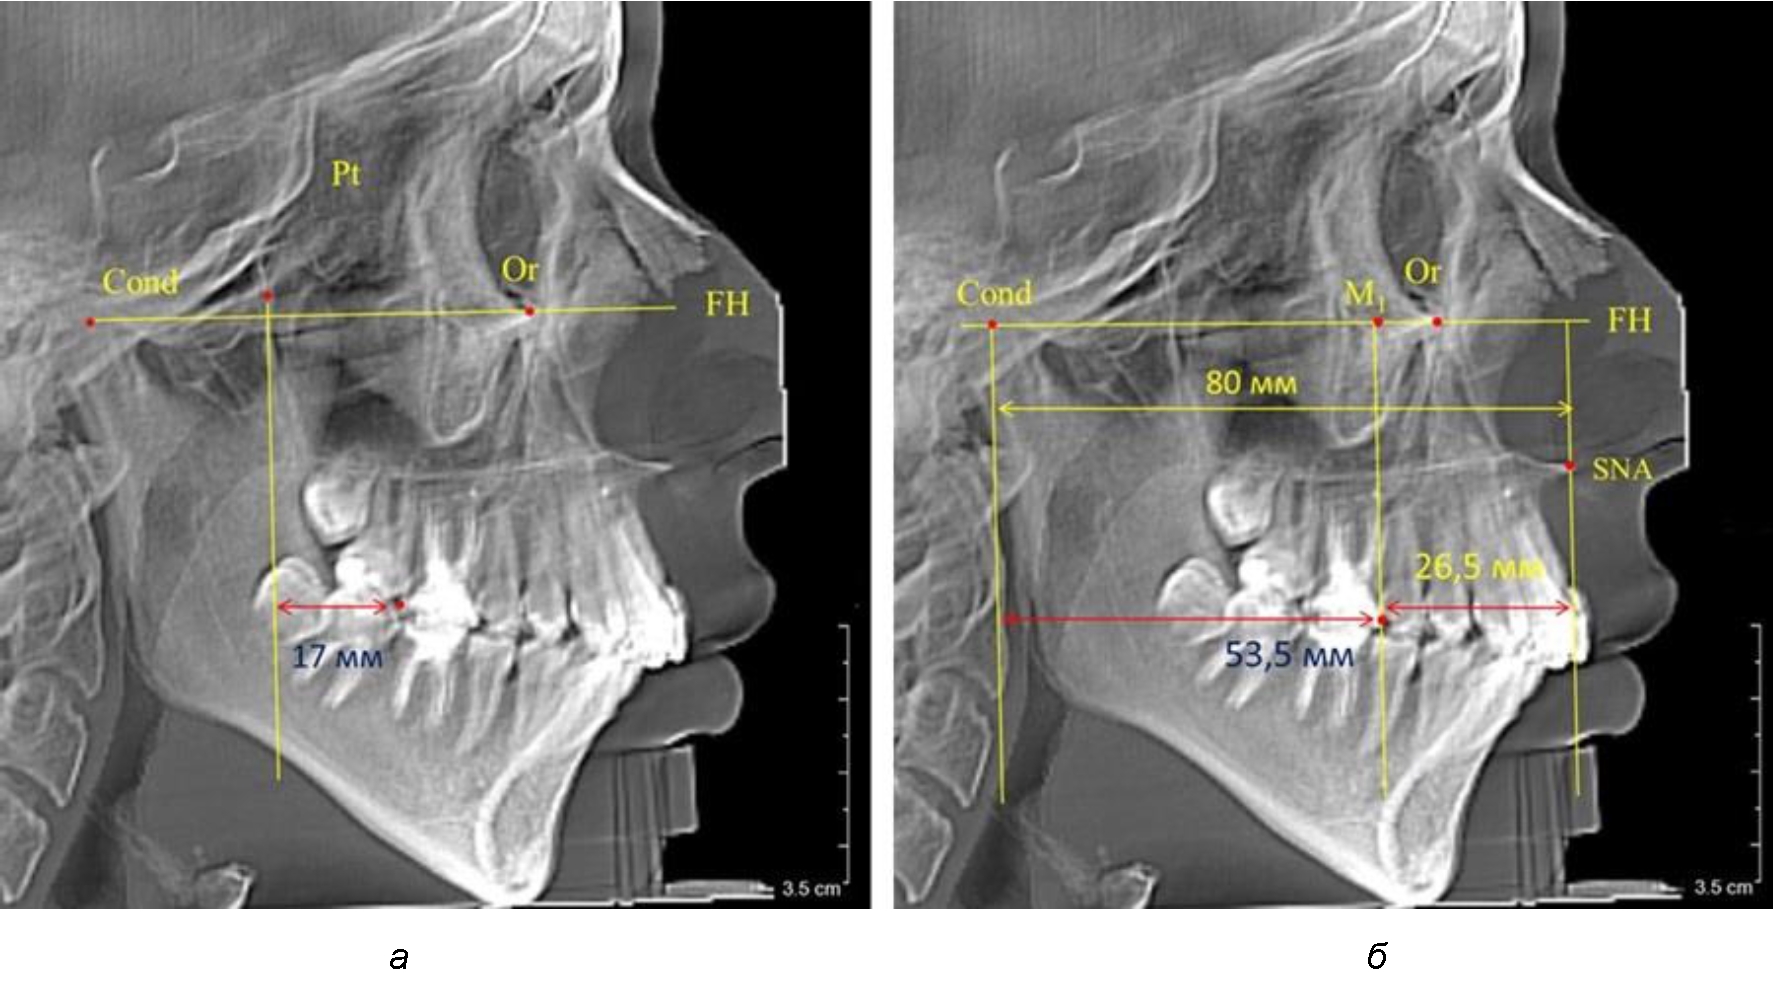

При проведении анализа к Франкфуртской горизонтали проводили передний и задний перпендикуляры. Передний спинальный перпендикуляр проходил через выступающую точку передней носовой ости (spina nasalis anterior – SNA), а задний суставной перпендикуляр опускали из кондилярной точки Cond. Молярный перпендикуляр проводили через медиальную поверхность первого постоянного моляра. Указанная вертикаль отделяла замещающие зубы постоянного прикуса от добавочных зубов (постоянных моляров), что вполне логично для анализа положения первых постоянных моляров в гнатическом комплексе (рис. 1).

Рис. 1. Метод определения положения первых верхних моляров по Ralph E. McDonald (а) и по предложенному методу (б)

Анализ проведенного исследования рентгенограмм показал существенную вариабельность практически всех линейных показателей. У молодых людей с физиологическим прикусом постоянных зубов расстояние от крыловидной вертикальной плоскости PTV до дистальной поверхности верхнего первого постоянного моляра в целом по группе составляло (18,37 ± 3,62) мм. Обращает на себя внимание большая ошибка репрезентативности из-за разницы между максимальными и минимальными значениями.

Среди анализируемых рентгенограмм минимальное значение расстояния по методу R. E. McDonald было 12 мм, а максимальное достигало 25 мм, что, по нашему мнению, обусловлено вариабельностью сагиттального размера гнатического отдела лица.

Так, при расстоянии от крыловидной вертикальной плоскости PTV до дистальной поверхности верхнего первого постоянного моляра в 13 мм сагиттальный размер гнатического отдела был 82 мм. При этом отношение кондилярно-спинального расстояния к кондилярно-молярному размеру (54,5) было близким к коэффициенту 1,5, что представлено на рис. 2.